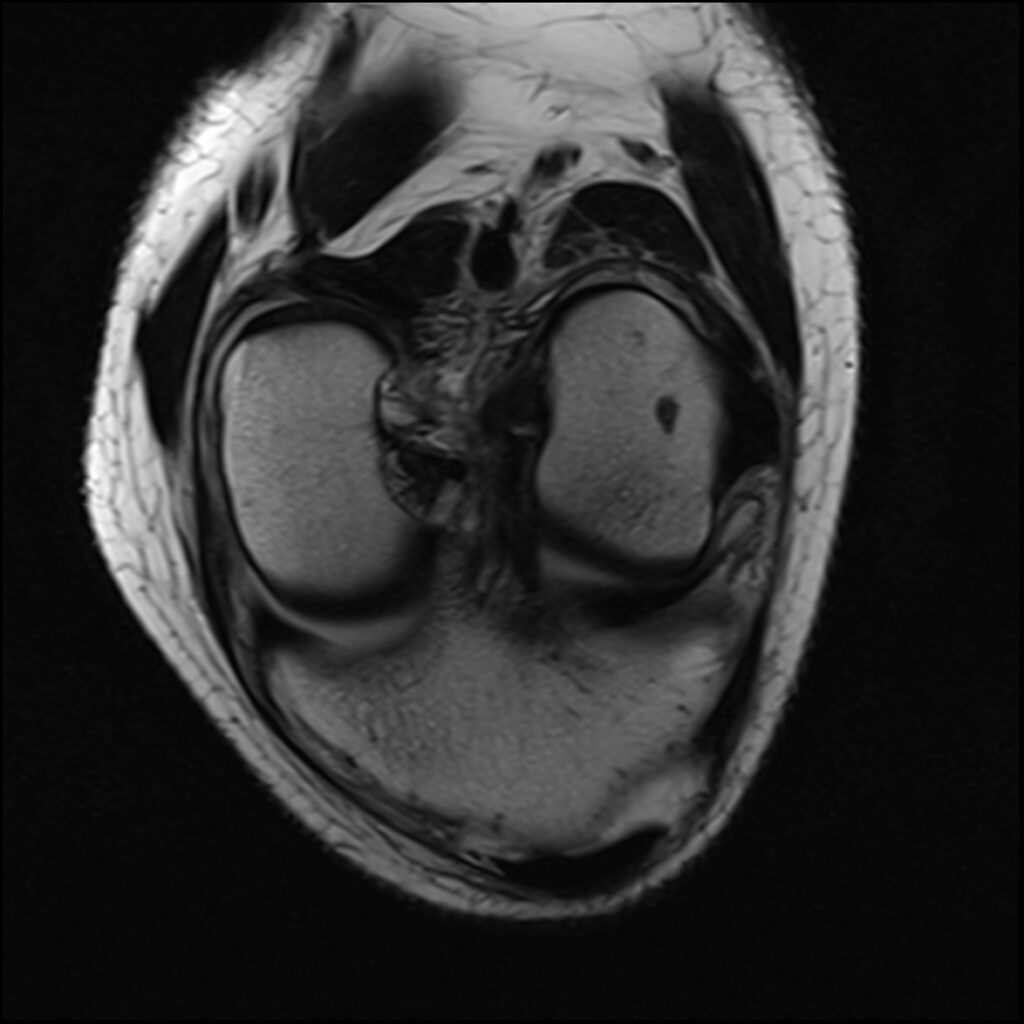

Patient C, age 44, was jumping on a trampoline when her foot got caught during rebound landing and forced the knee to extend and twist, tearing her ACL and medial meniscus and causing a Segond’s fracture, a posterolateral compression injury seen on the T2 sagittal MR images. Immediately upon becoming aware of her ACL injury, she asked my staff if she could put her “before & after” MR scans on my practice’s website after it healed. The initial treatment and aftercare were the same as patient D, aspirating any effusion and treating the posterolateral origin of the ACL. At 8-week follow-up, her knee was treated with hypertonic dextrose, with the collateral ligaments being treated with DGP. She was treated again at 16 weeks with another autologous PRP treatment of the knee joint, ligaments, and tendons. She was released to full sports and activities at 18 weeks post-injury. Subsequent MR scan revealed complete recovery of her ACL. Low grey signal replaced the original high signal intensity tear in the meniscus, appearing healed. Her knee was reported to be symptom-free at 5-year follow-up.

Patient C Before

Patient C After